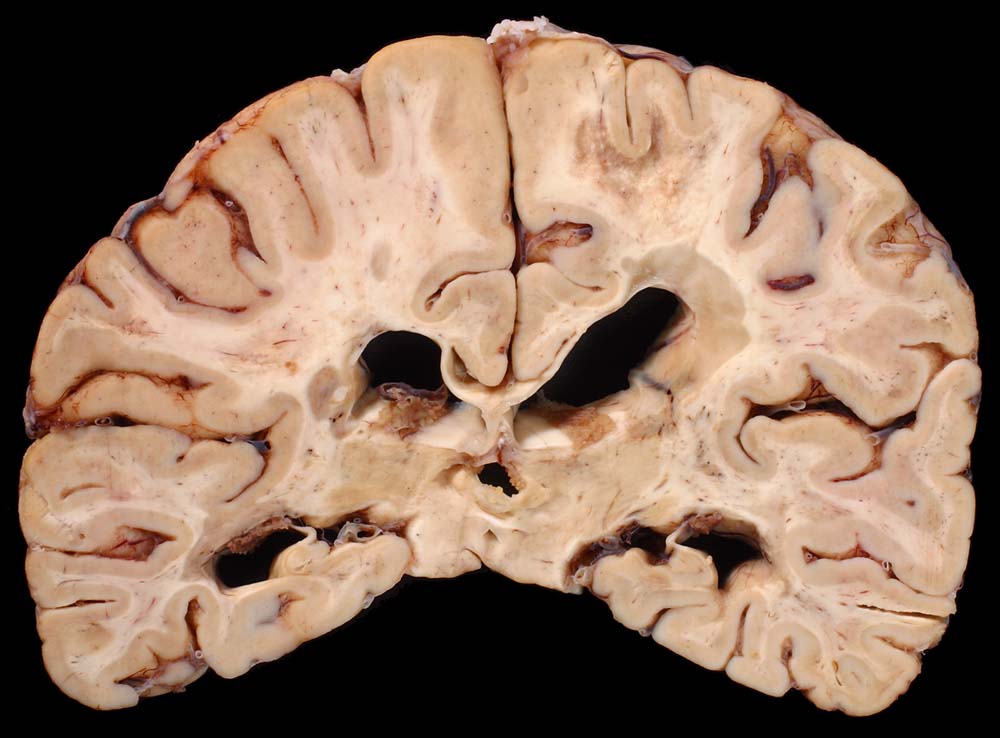

PathoPic – image database / PathoPic ID 8684 - Entmarkungsherde bei Multipler Sklerose

Entmarkungsherde bei Multipler Sklerose

Periventrikulär betonte fleckförmige Grauverfärbung des Marklagers ( Entmarkungsareale).

Chronische und aktive Entmarkungsareale in der weissen Substanz (beidseits, periventrikulär betont).

Diagnose einer multiplen Sklerose vor 12 Jahren. Paraparese der Beine. Neurogene Blasenentleerungsstörung. Seit einem Jahr deutliche neurologische Verschlechterung.